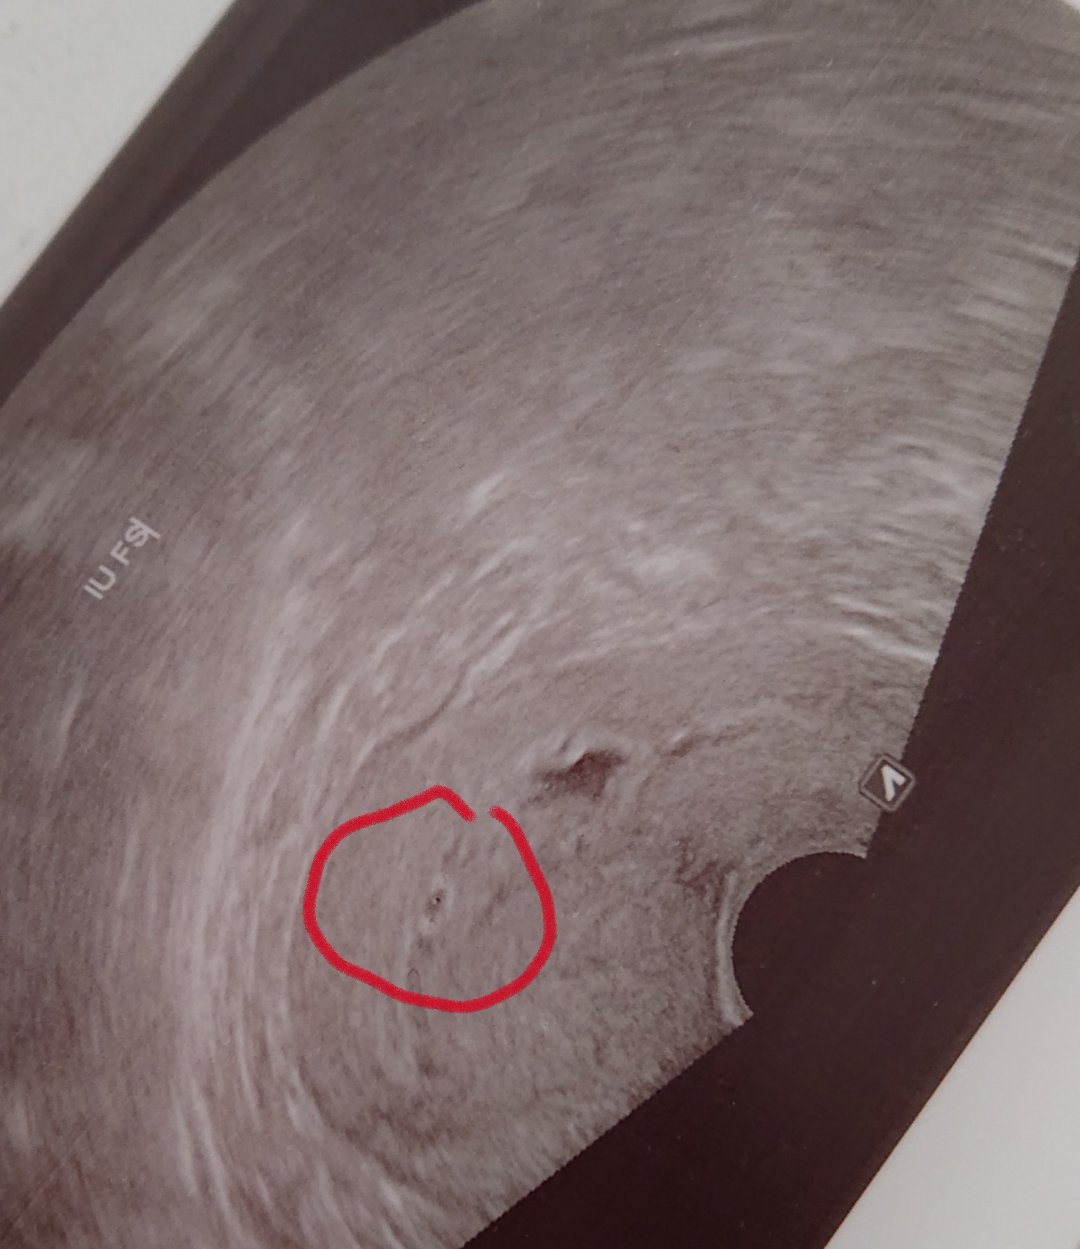

Hematom sa nachadza v dolnej oblasti dolneho polu pl. Vajca drobec ma 10,78 mm a hematom 10x14 mm hned pod nim

Ahojte chcem sa spýtať aké mate skusenosti s hematomom ? Dnes mam ukonceny 7 tt a vraj mam hematom 14x10mm v oblasti dolneho polu mate skusenosti ? Bojim sa o malicke zatial nespinim ani nič ani som o nom nevedela :(